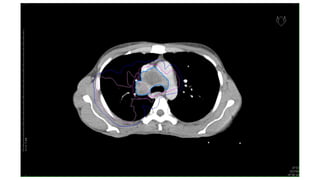

NSCLC

CT images ofCa Lungs